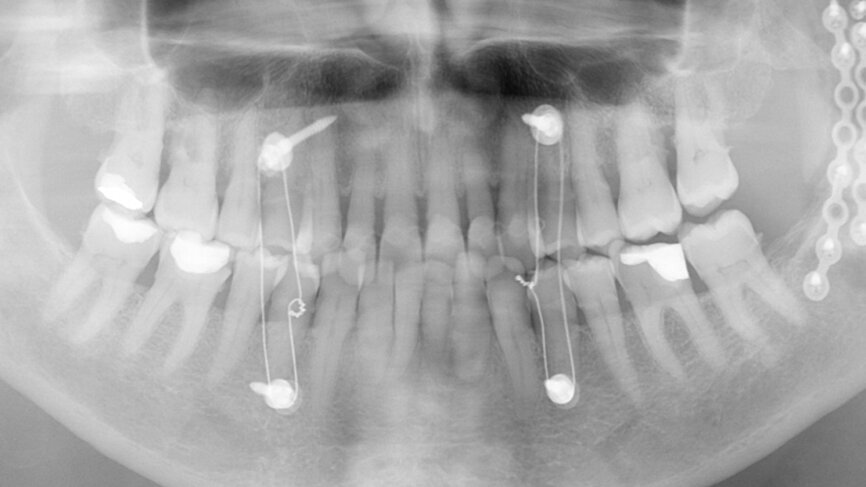

Fig. 13: Final radiograph used to check for excess cement around the bridge.